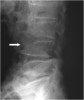

압박골절 시에는 lateral X-ray 검사에서 추체 전방부 높이가 낮아지므로 후만 기형(kyphotic deformity)이 발생합니다. 방출형 골절(burst fracture)은 CT에서 가장 잘 나타납니다. 불안정한 굴곡-신연 손상 시에는 AP, lateral X-ray에서 극돌기 사이의 간격이 벌어집니다. AP view에서 횡돌기 골절이나 불안정한 방출형 골절로 인한 척추경 사이 간격(interpedicular distance)이 넓어짐을 확인할 수 있습니다. 한 추체가 아래 추체에 비해 돌아가 있는 것도 척추 불안정성을 시사합니다. 단순 압박골절 이외에도 어떠한 부상이 있다면 추가적인 영상이 필요할 것입니다.

X-ray : 흉추/요추 골절(Fractures of the Thoracic or Lumbar spine)